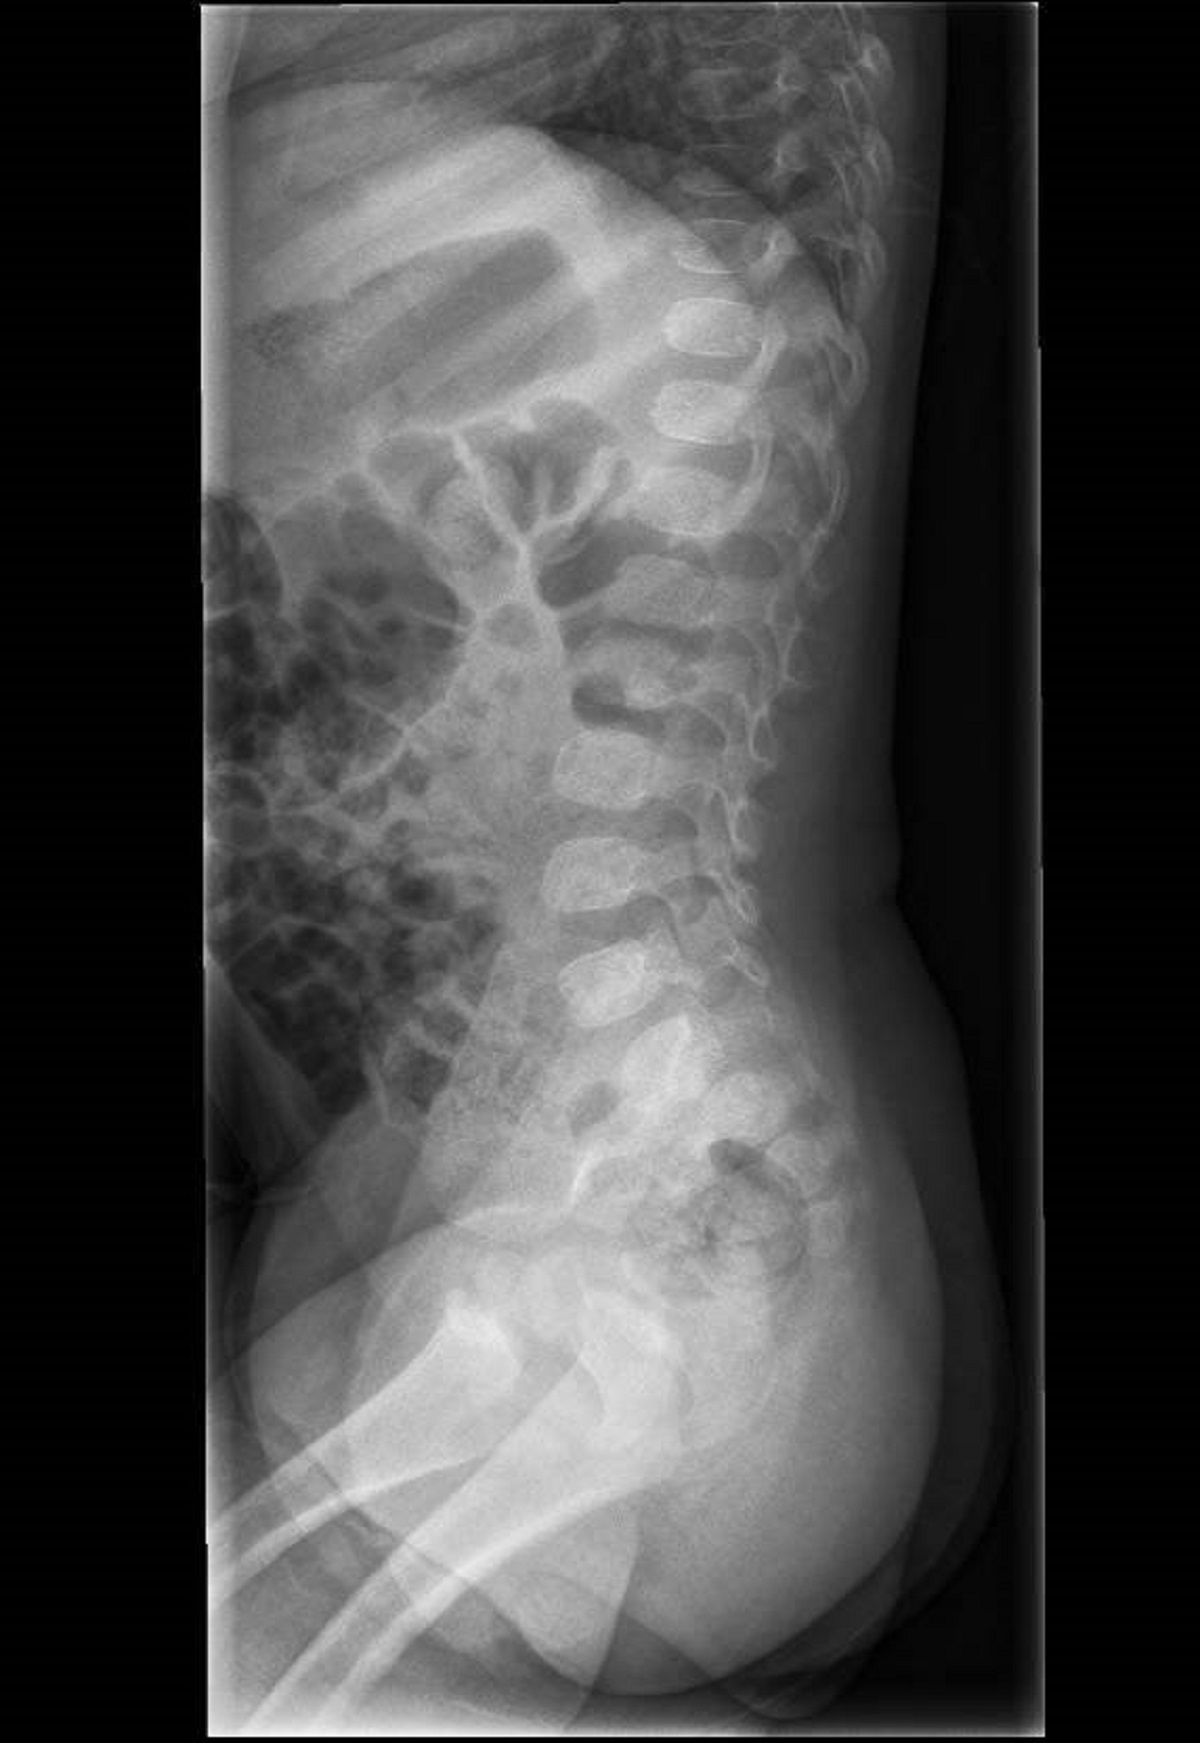

Niña de 15 meses, sin antecedentes médico-quirúrgicos de interés, que acude por irritabilidad, rechazo de deambulación y sedestación de 2 semanas de evolución asociado a estreñimiento de 4 días. Afebril en todo momento. A la exploración destaca dolor a la palpación en apófisis espinosas lumbares. A la deambulación adopta una postura antiálgica con hiperlordosis. Se practica radiografía lateral de columna (Figura 1) y RNM con contraste i.v. (Figura 2).

Figura 1. Radiografía de columna lumbar en proyección lateral en la que se aprecia disminución del espacio intervertebral T12-L1 y L1-L2.